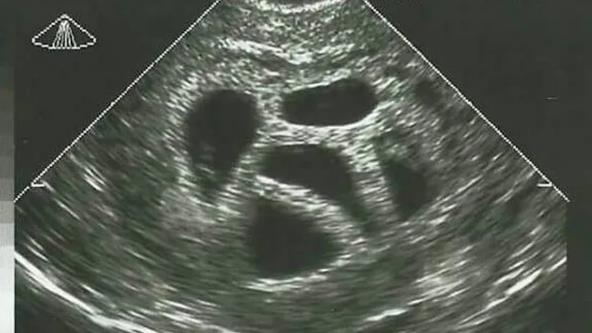

U svetu u kojem se svaka odluka o životu pretvara u debatu, priča Amerikanke Suzan Tompson vraća fokus na ono što je suštinsko - na veru, ljubav i hrabrost da se veruje u nemoguće. Imala je samo 28 godina kada je saznala da nosi petorke. Lekari su bili direktni; savetovali su joj selektivni abortus, objašnjavajući da je trudnoća rizična i da "nije realno" da sva deca prežive.

"Moj ginekolog mi je više puta predlagao da razmislim o smanjenju broja embriona - da abortiram troje, možda dvoje dece. Ali moj muž i ja nismo o tome ni pomislili. Znali smo da, ako ih je Bog poslao, On će se i pobrinuti za njih", prisetila se Suzan.